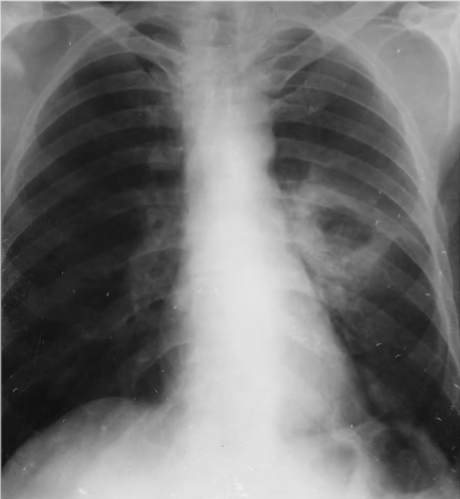

Rx toracică, incidență P-A

DESCRIERE:

la niv. întregului hemitorace dr → opacitate extinsă, nesistematizată, de intensitate mare, omogenă

caracter retractil → tracționează traheea și mediastinul de partea afectată

fără bronhogramă aerică

la niv. hemitoracelui stg → opacități nodulare multiple de dimensiuni variabile, intensitate medie-mare, omogene, cu contur net

DX: atelectazie prin NBP central endobronșic pe bronhia principală dreaptă + MTS pulmonare hematogene

DD:

hidatidoză

pleurezie masivă - caracter expansiv